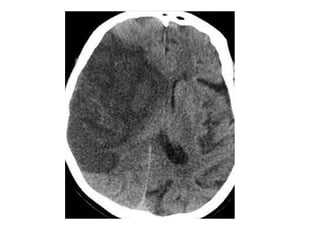

NECT shows hyperdense internal veins and bilateral (R > L) thalami

hypodensities , compatible with dural vein thrombosis and venous